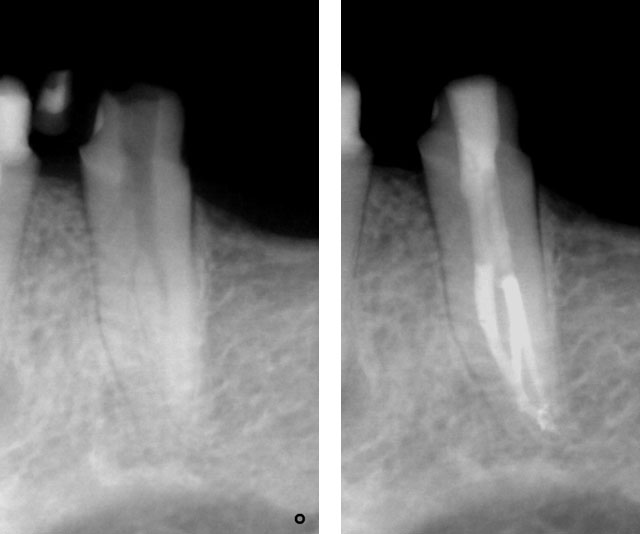

Clinical Case

Pre-op:

Central incisor referred after previous clinician had accessed the tooth and was unable to locate the calcified canal.

Removal of temporary restoration shows palatal perforation (red arrow) and a calcified canal in the middle (yellow arrow)

Palatal perforation was supra-crestal and was repaired with GIC

Calcified canal located

Calcium hydroxide placed

Recall after 10 days. Sinus tract healed

Post-op & 1 year recall

Pre-op, Post-op & 1 year recall